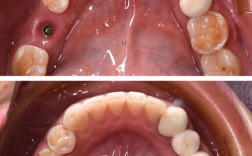

(图片来源网络,侵删)

(图片来源网络,侵删) -